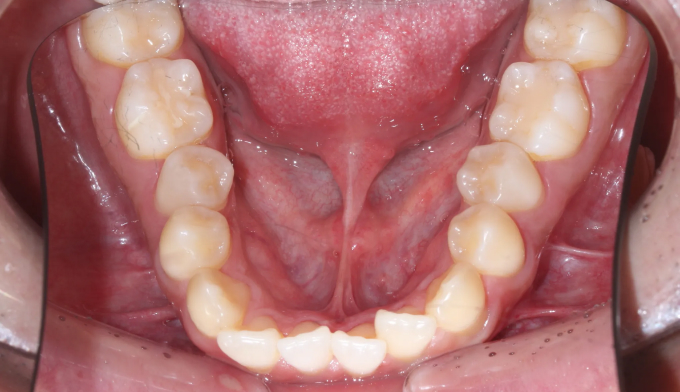

주걱턱과 돌출입, 그리고 덧니를 한꺼번에 가지고 있는 경우입니다. 이 모두를 해결하기 위해서는 필요한 공간의 양이 많기 때문에 성인에서는 작은어금니 발치가 대부분 필요합니다.

교정치료를 통해 치열이 고르게 된것은 물론, 주걱턱과 돌출입이 개선되면서 입술 모양이 보다 더 자연스러워지고 안모가 개선되었습니다.

총 교정치료는 21개월입니다.